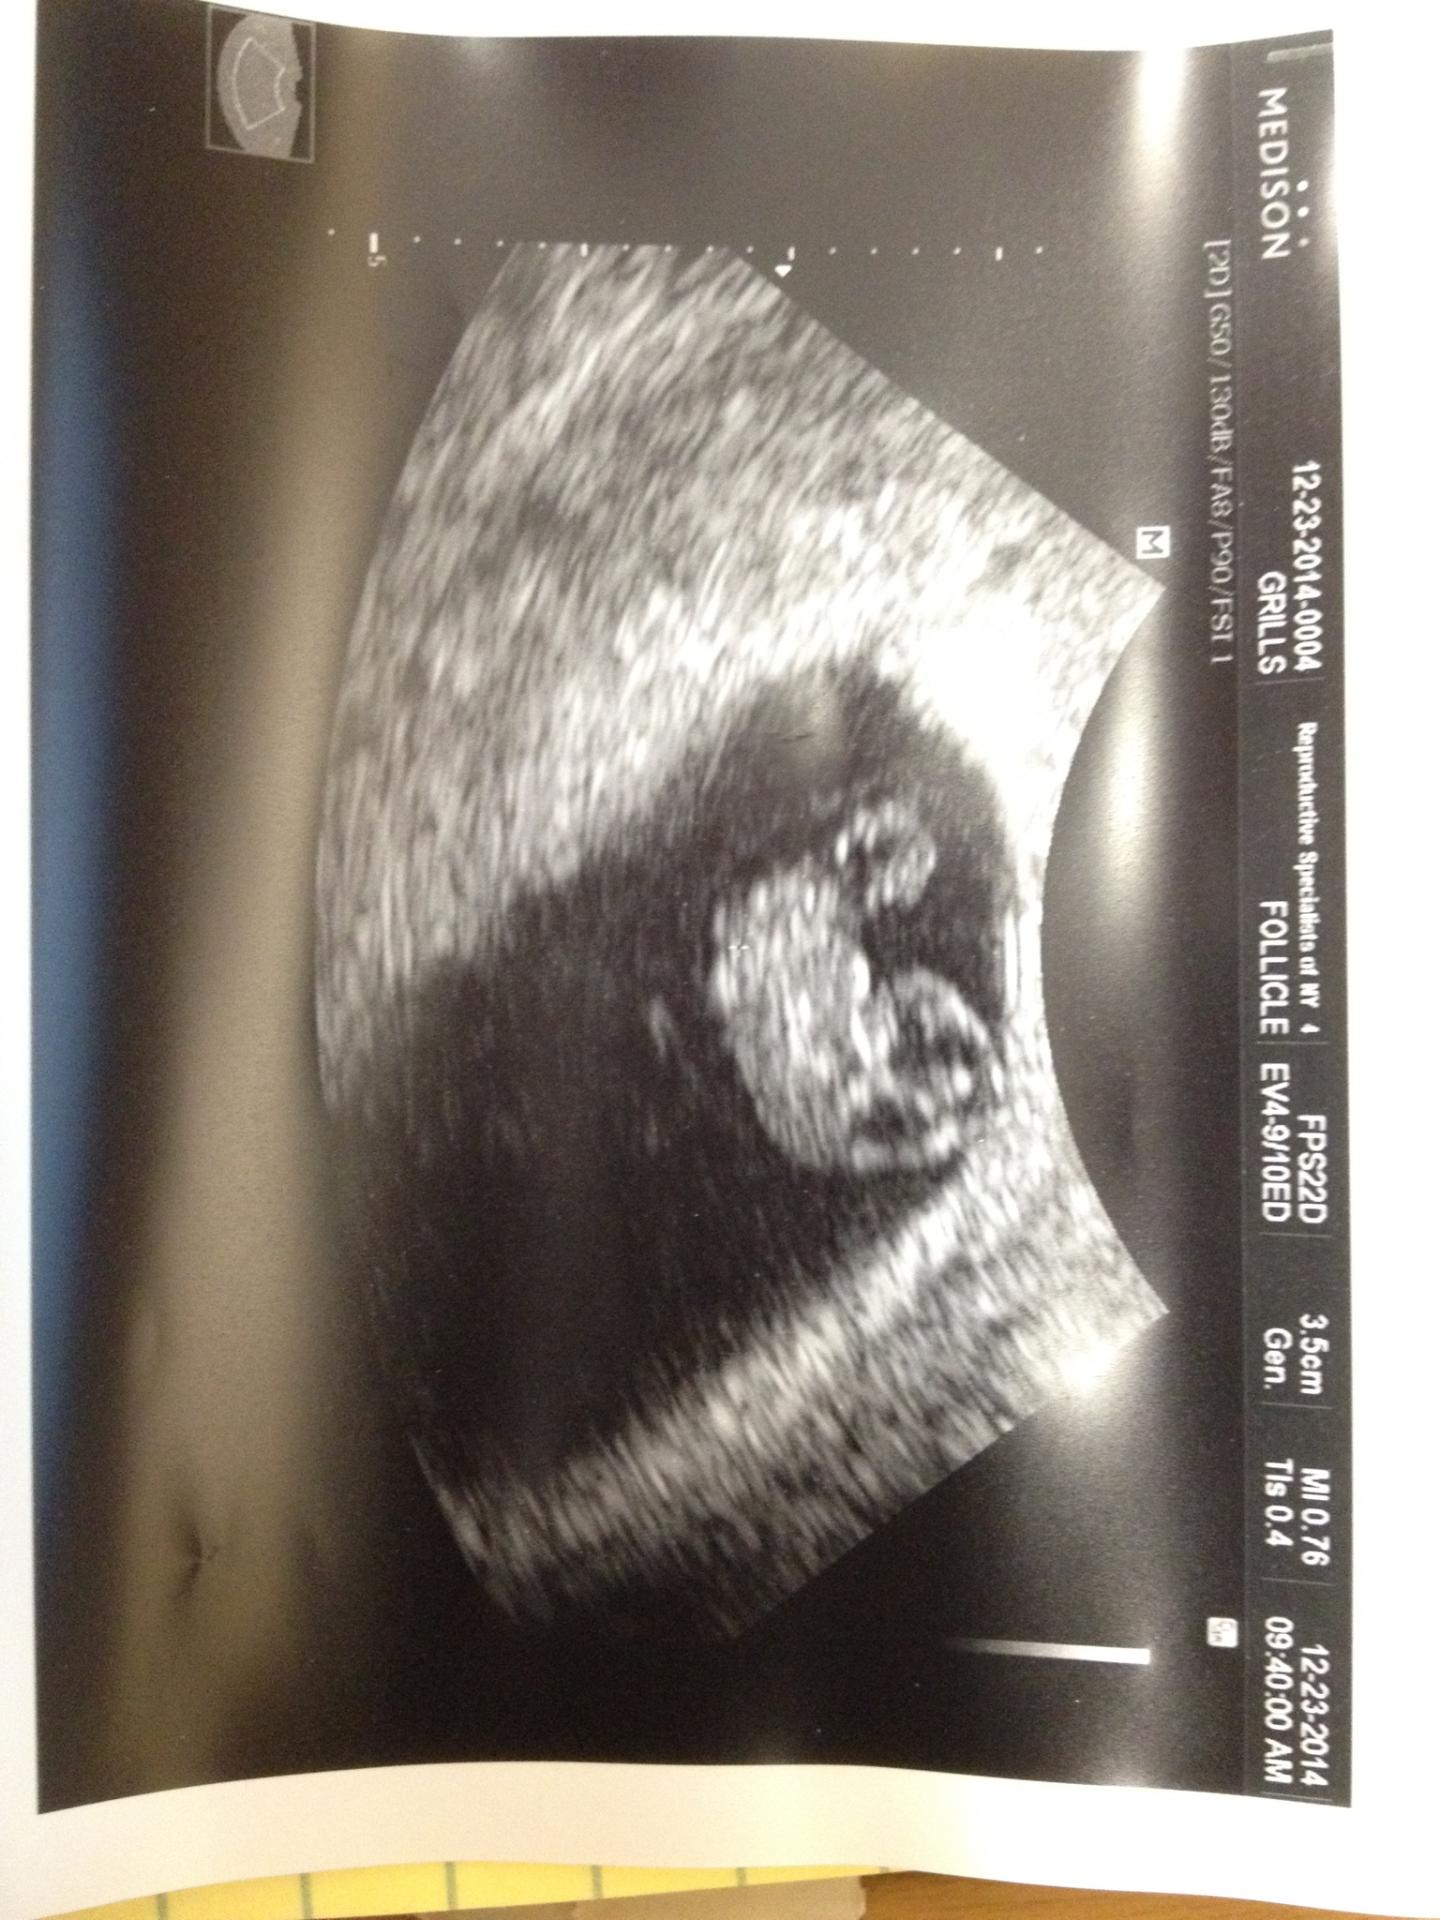

Today I had my 3rd ultrasound for this pregnancy. The baby is measuring a couple days ahead at 8 weeks (when FF puts me at 7w5d) with a heartrate of 176 bpm.

And now for a sideways picture!